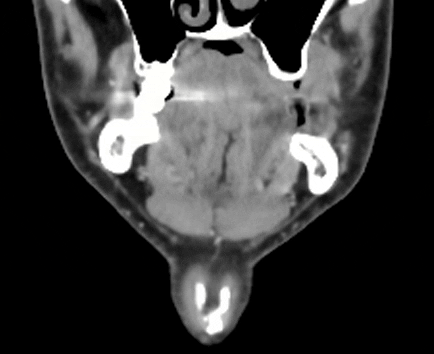

- Finally, my oral surgeon spotted something on the dental CBCT and asked me to check if I have ES. So, I did the CT for ES and it revealed a calcified portion of the stylohyoid ligament.

And, before we proceed, I literally looked at the 3D rendered CT today, and the calcified portion is only ~15mm, detached from styloid process, and about 1.5mm from C1. In the CT results, it says “partially calcified stylohyoid ligament, combined length 31mm” but the keyword there is “combined.”

Sagittal view. Calcified portion of stylohyoid ligament. There is a little bit more in another slice, but this is the most of it.